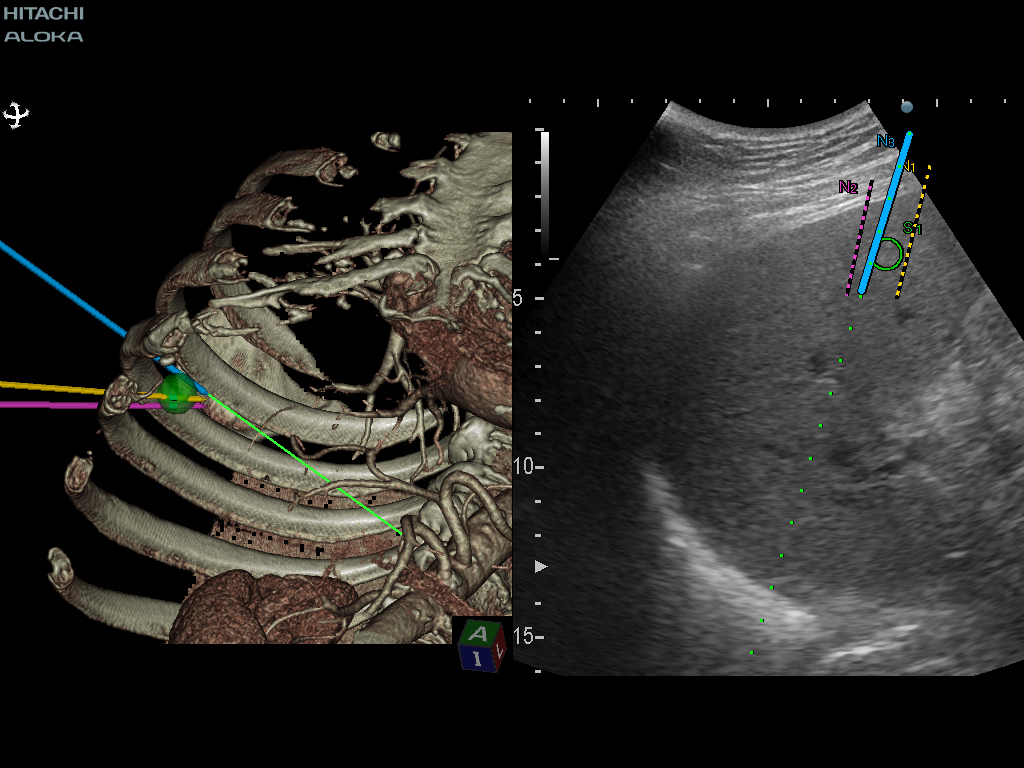

생검 계획 및 중재 적 지원을 위해 표시된 목표 경로와 바늘 경로 사이의 위치 관계.